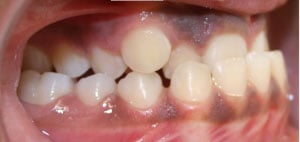

Crossbite

A crossbite occurs when one or more of the upper teeth bite on the inside of the lower teeth. It can occur in the front of the mouth or on the sides, where its usually a bilateral condition. Early correction of a crossbite is recommended because it can lead to permanent problems including asymmetric jaw growth, irregular muscle function and altered tooth eruption.

Crossbite should be corrected because it can:

- cause premature wear of the teeth

- cause gum disease including bone loss

- cause asymmetrical development of the jaws

- cause dysfunctional chewing patterns

- make your smile less attractive

How can a crossbite be orthodontically corrected?

If there is a single tooth in crossbite, the tooth can be moved into the correct position with braces. When multiple teeth are in crossbite, the arch needs to be expanded with braces or a combination of braces and an intra-oral appliance. This will help correct the bite relationship and allow the jaws to grow in harmony.

Before and After photos: Crossbite Treatment